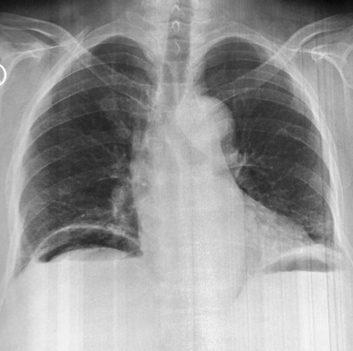

Complication perfore une

ulcer gastroduodenal est image de croissance gasseuse

sous diapragmatique droit . Cliche de face AP |

Sur la TDM en coupe axiale , c'est image

de air libre a espace superieure de l'abdomen .

Ulcere de la face anterieure duodenum perfore |